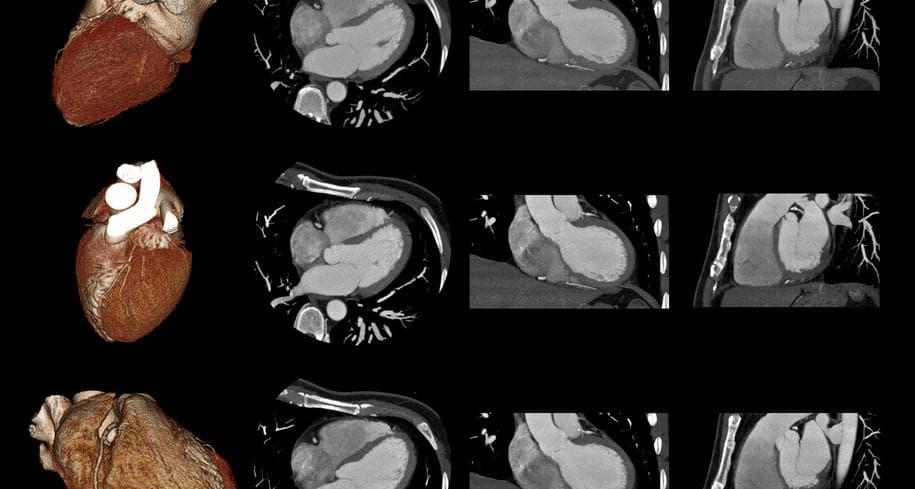

Negli ultimi dieci anni, l’impiego delle indagini radiologiche in ambito cardiologico è cresciuto in maniera esponenziale, grazie all’importanza delle informazioni fornite. Questa evoluzione ha portato i cardiologi a rivedere le indicazioni diagnostiche tradizionali, integrando agli esami di base (Visita cardiologica, Elettrocardiogramma, Ecocardiocardiogramma CD,  e Test da sforzo) anche accertamenti di secondo livello, come la TC coronarica e la Risonanza magnetica cardiaca.

Per accogliere le necessità di questi pazienti  è nato, presso la Casa di Cura San Francesco, il percorso di Imaging Cardiologico Integrato: un approccio multidisciplinare coordinato dalla dottoressa Francesca Besana (radiologa) e dalla dottoressa Elena Perlasca (cardiologa), che collaborano per fornire ad ogni paziente un iter diagnostico-terapeutico completo e personalizzato.